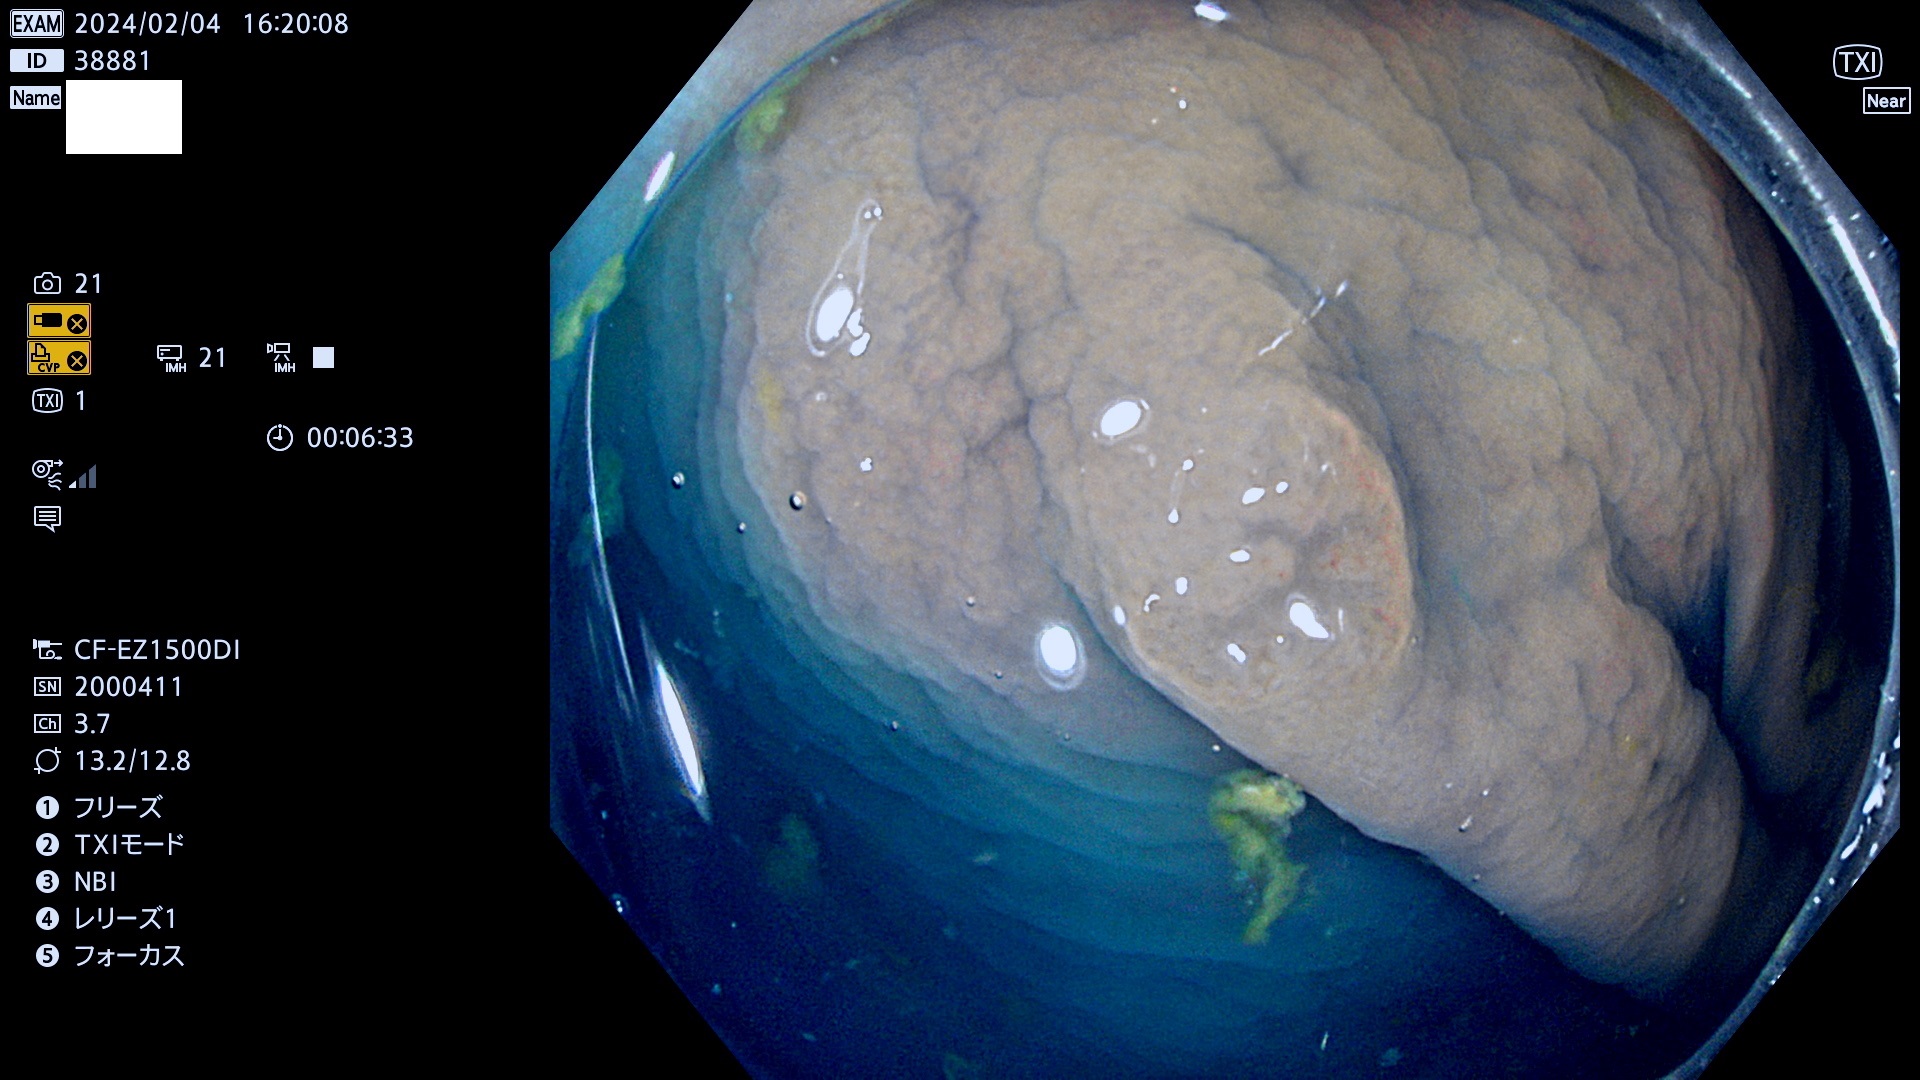

表面型腺腫(Flat Adenoma)の中で、完全に平坦な物をUb、陥凹している物をUcと呼びます。平坦隆起型(Ua)よりも、発見が難しく危険な病変です。

毎週の検査(木・金・土・日)に発見されたUb、Uc型・腺腫を、その週の日曜の夜にUPし1週間、提示します。

抽出の対象期間 2024年2月1日(木)〜2月4(日)の4日間(40件の検査)12件